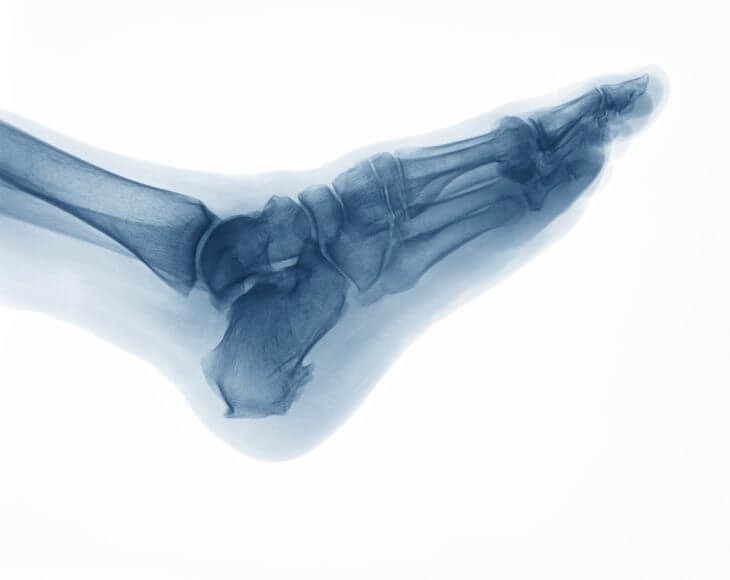

Дополнительно пациента отправят на рентген пятки. Благодаря такой процедуре доктор поймет размер шпоры, ее состояние и точное местонахождение. Иногда шпора не вызывает болевых ощущений и обнаруживается на рентгене случайно при диагностике другого заболевания.

На снимке рентгена врач увидит изогнутый шип в области пятки. На первой стадии болезни шпора будет округлой формы. Впоследствии нарост увеличивается и может достигать длины до 11-12 мм. При запущенной стадии шпора становится по форме, как клюв птицы.

Доктор может дополнительно потребовать от пациента посетить МРТ. Такая диагностика поможет увидеть состояние тканей вокруг шпоры. Можно также использовать УЗИ пяточной зоны. Однако к такому методу диагностики прибегают довольно редко. Обычно УЗИ посещают в процессе терапии, чтобы контролировать выздоровление.